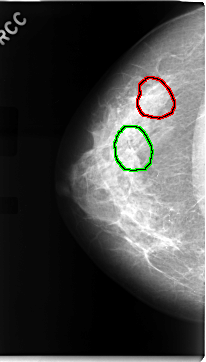

FILE: C_0068_1.RIGHT_CC.OVERLAY

TOTAL_ABNORMALITIES 2

ABNORMALITY 1

LESION_TYPE CALCIFICATION TYPE AMORPHOUS DISTRIBUTION CLUSTERED

ASSESSMENT 5

SUBTLETY 4

PATHOLOGY MALIGNANT

TOTAL_OUTLINES 1

BOUNDARY

ABNORMALITY 2

LESION_TYPE MASS SHAPE ARCHITECTURAL_DISTORTION MARGINS SPICULATED

ASSESSMENT 4

SUBTLETY 2